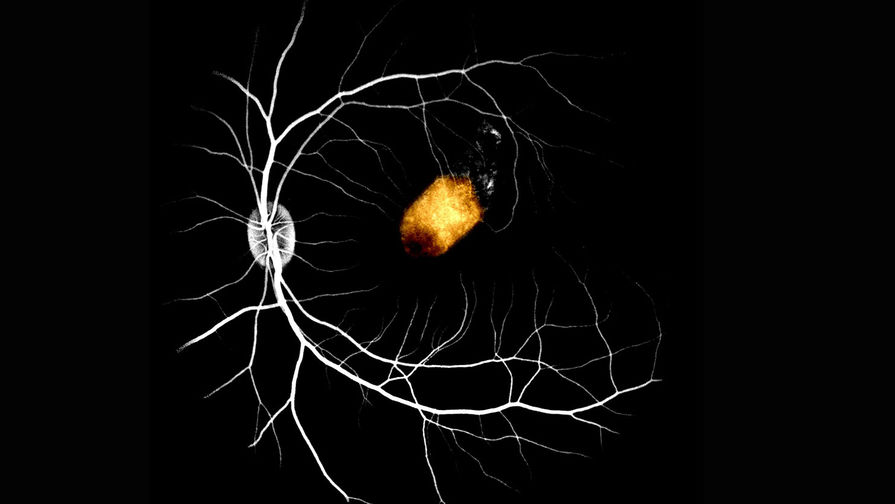

Пигментный эпителий сечтатки из стволовых клеток глаза человека, пересаженный на сетчатку макаки

Исследователи использовали стволовые клетки сетчатки, полученные от двух умерших пожилых людей. Они пересадили их на желтое пятно — место наибольшей остроты зрения в сетчатке — девяти макак. Эксперимент проводился пока что на здоровых животных, чтобы понять, возможна ли вообще подобная пересадка. Клетки успешно прижились, на протяжении трех месяцев не наблюдалось никаких серьезных побочных эффектов.

Более того, пересаженные клетки оказались способны взять на себя функции пигментного эпителия сетчатки обезьян, что дает потенциальную возможность в будущем использовать такой метод для борьбы со слепотой.

«Мы продемонстрировали, что пигментный эпителий сетчатки, полученный от человеческих трупов, способен по крайней мере частично взять на себя функцию желтого пятна у приматов, — говорит автор статьи и клеточный биолог Тимоти Бленкинсоп. — Клетки, полученные от мертвого донора, можно безопасно трансплантировать под сетчатку и компенсировать ее функцию у хозяина, поэтому их применение для борьбы с потерей зрения у пациентов с заболеваниями сетчатки выглядит очень многообещающе».